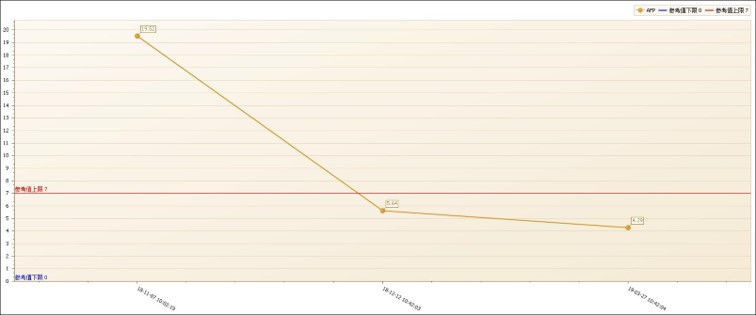

AFP情况

2019-11 复查AFP正常。

2018-10-26 2019-5-31 2019-11-6

术前 左肝肿物切除, 复查无复发

术后病理:凝固性坏死